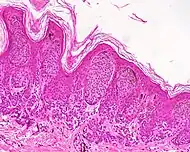

| Dysplastic nevus | Usually a compound nevus with cellular and architectural dysplasia. Like typical moles, dysplastic nevi can be flat or raised. While they vary in size, dysplastic nevi are typically larger than normal moles and tend to have irregular borders and irregular coloration. Hence, they resemble melanoma, appear worrisome, and are often removed to clarify the diagnosis. Dysplastic nevi are markers of risk when they are numerous, such as in people with dysplastic nevus syndrome. According to the National Institute of Health (NIH), doctors believe that, when part of a series or syndrome of multiple moles, dysplastic nevi are more likely than ordinary moles to develop into the most virulent type of skin cancer called melanoma.[22] | ![]() In this case, the central portion is a complex papule, and the periphery is macular, irregular, indistinct and slightly pink. |

Characteristic rete ridge bridging, shouldering, and lamellar fibrosis. H&E stain.